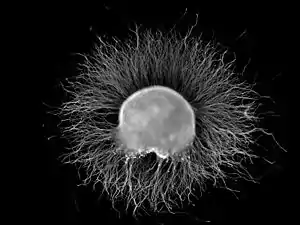

Ganglion

A ganglion (PL: ganglia) is a group of neuron cell bodies in the peripheral nervous system. In the somatic nervous system this includes dorsal root ganglia and trigeminal ganglia among a few others. In the autonomic nervous system there are both sympathetic and parasympathetic ganglia which contain the cell bodies of postganglionic sympathetic and parasympathetic neurons respectively.

Ganglia are primarily made up of somata and dendritic structures which are bundled or connected. Ganglia often interconnect with other ganglia to form a complex system of ganglia known as a plexus. Ganglia provide relay points and intermediary connections between different neurological structures in the body, such as the peripheral and central nervous systems.